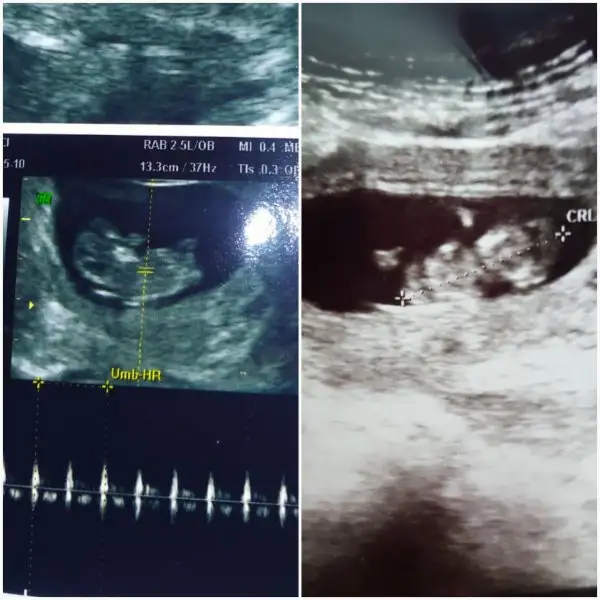

Mesela bu görüntüde benimkini açıklıyo. Ben bu acıdan görebildim cunku. Üstten ve bacak arasından. Benımkını yandan görmedim ben.

Hay yorumunu seveyim çokta ümitlenmek istemiyorum ama benim ilk 17 haftalıktı diğeri 22 haftalıktı gösterdiler erkek olmalarına rağmen geç gösterdiler çünkü doğru pozisyon yoktu ama dediğin gibi bunun bariz bacak arası kısmı belirgin ve çıkıntı yok işin garibi 10 haftada da çıkıntı vs yoktu hep o kısım açık bunda utanmaz mıdır nedir bu kız şimdi bak çok kızdım:halay:yerim onu ben